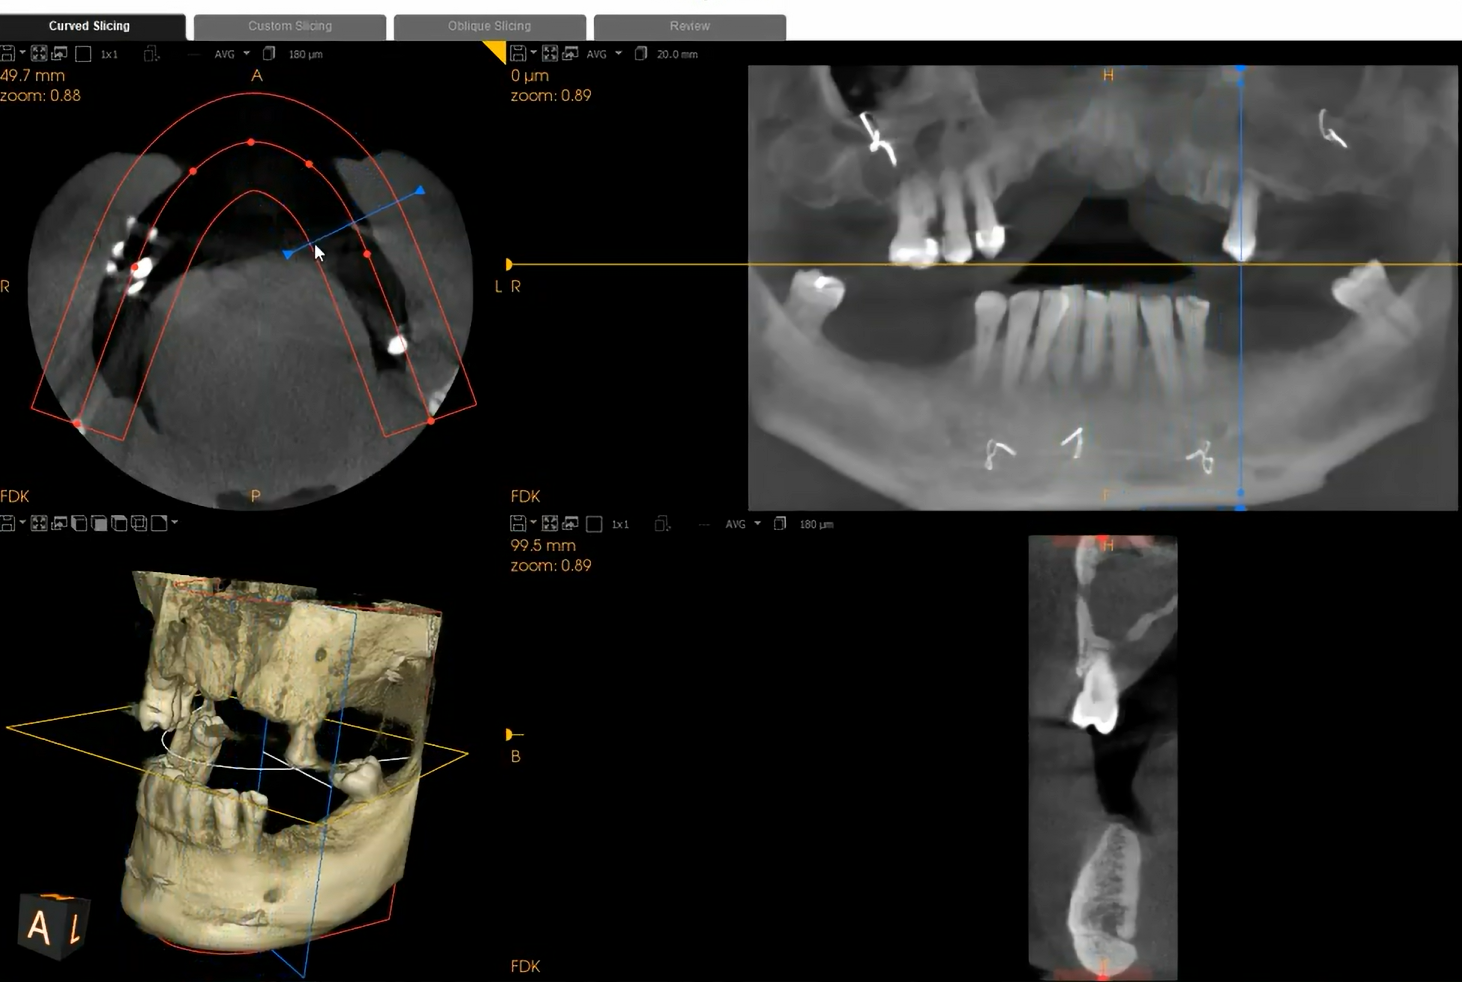

Our CBCT scanning system helps us get a detailed, 360-degree view of the jaw, nerves, gums, and soft tissue. The information we can collect via computed tomography goes far beyond that of a traditional X-ray, helping our dental team properly place, type, and design implants.

Using 3D imaging, we can check the bone density and jaw health and plan the installation to the finest detail, including predicting what sort of aftercare might be necessary during the healing process. The scan includes the sinuses, nasal cavity, and nerve canals, so you can feel confident that the prosthodontist working with you has a full overview of any nerves that might be affected by the installation of dental implants.

Our dentists and dental technicians take a patient-centered approach to care, starting with CBCT scanning. With this type of diagnostic, you’ll receive a lower dose of radiation than you would from a traditional dental scan, and you’ll get more detailed results.